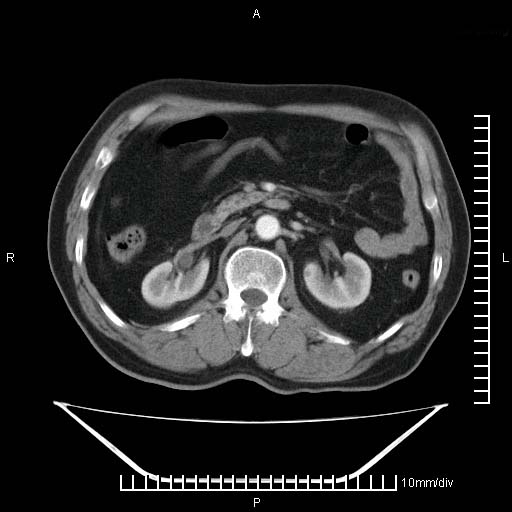

标题: CT25082:肝脏增强:男性,70岁 [打印本页]

标题: CT25082:肝脏增强:男性,70岁

患者以心脏疾病收住院,腹部无明显症状,b超查肝脏有占位。

牛眼征,中心坏死无强化,外缘强化,最外缘又见低密度,考虑转移,与脓肿鉴别

肝内多发转移瘤,右下肺炎症并少量胸水。胃壁增厚建议胃镜,胰尾部“病变”为肠管。

1)肝脏多发性转移瘤(不排除胰尾癌转移所致可能)。2)腹水。3)右侧少量胸腔积液。

右下胸膜肥厚。

胰尾占位?结肠脾曲?

ct25082 结果:转移瘤

外院mr结果:胰尾恶性占位。